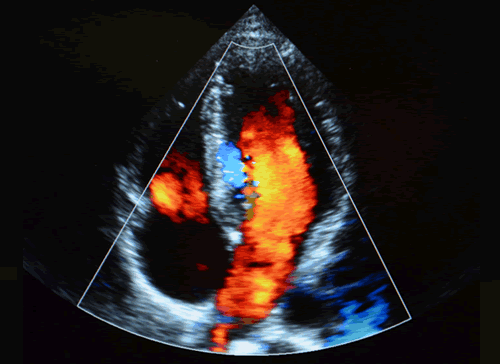

4.弁の形態とエコー像

1.心機能計測のポイントと注意点